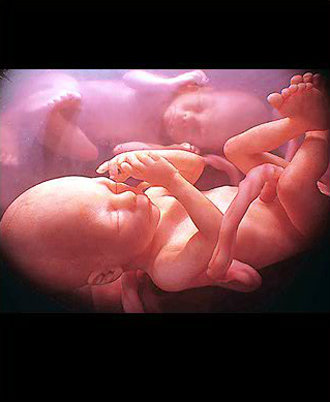

- 양수검사 (분만시 연령이 만 35세 이상, 기형 가족력이 있는 경우는 필수)